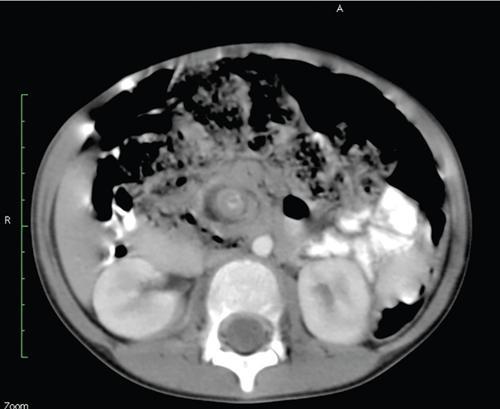

Fifty-year-old lady with vague upper abdominal discomfort.

Single contrast barium study (Fig. 7.4.5.1), CECT (Figs. 7.4.5.2 and 7.4.5.3).

Observations

Barium study shows large filling defect in the antrum forming acute angles with the wall. Undulating contour is seen along greater curvature with ulceration of overlying mucosal irregularity.

CECT shows a large lobulated mass involving lesser curvature and antrum with marked wall thickening along distal greater curvature.

Diagnosis

Carcinoma stomach.